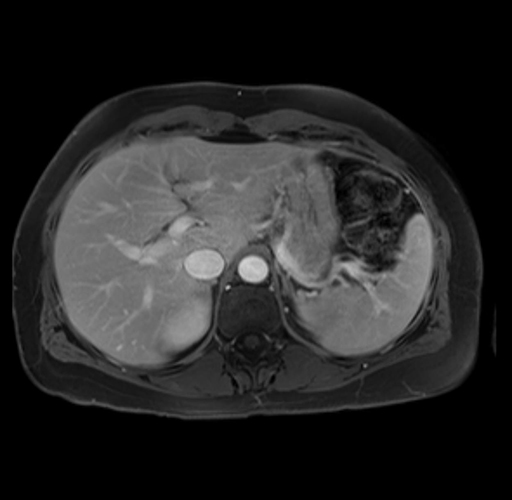

Imaging Analysis

Look through the patient's CT scan to identify any areas of concern for the necessary procedure.

Based on your CT findings, which issue(s) are present and would give reason for "planned slowing down moment(s)" in this case?

Considering a standard distal pancreatectomy procedure, what step(s) of the operation would you do differently in this case?